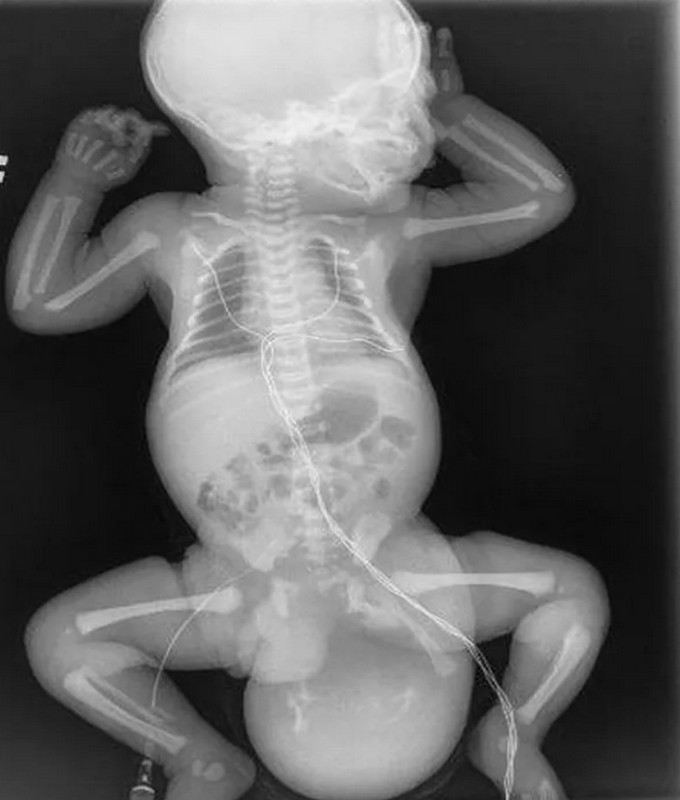

Хирурги Московского областного центра охраны материнства и детства удалили новорожденному мальчику опухоль, составлявшую треть его веса.

Хирурги Московского областного центра охраны материнства и детства удалили новорожденному мальчику опухоль, составлявшую треть его веса.  Операция была сложной, так как образование прилегало к прямой кишке и крупному сосудисто-нервному пучку. Вся анатомия ягодичной области была нарушена, перед медиками стояла задача буквально по миллиметру выделять эту опухоль.

Благодаря слаженной работе врачей удалось удалить тератому без повреждения близлежащих структур.

После удаления опухоли медики столкнулись с обширным дефектом тканей, который удалось укрыть, выполнив пластику местными тканями. С возрастом послеоперационный рубец станет более незаметным.

Удаленную опухоль направили на гистологию, которая показала, что она доброкачественная и содержала в частности фрагменты костной и хрящевой ткани, а также клетки волос и ногтей.